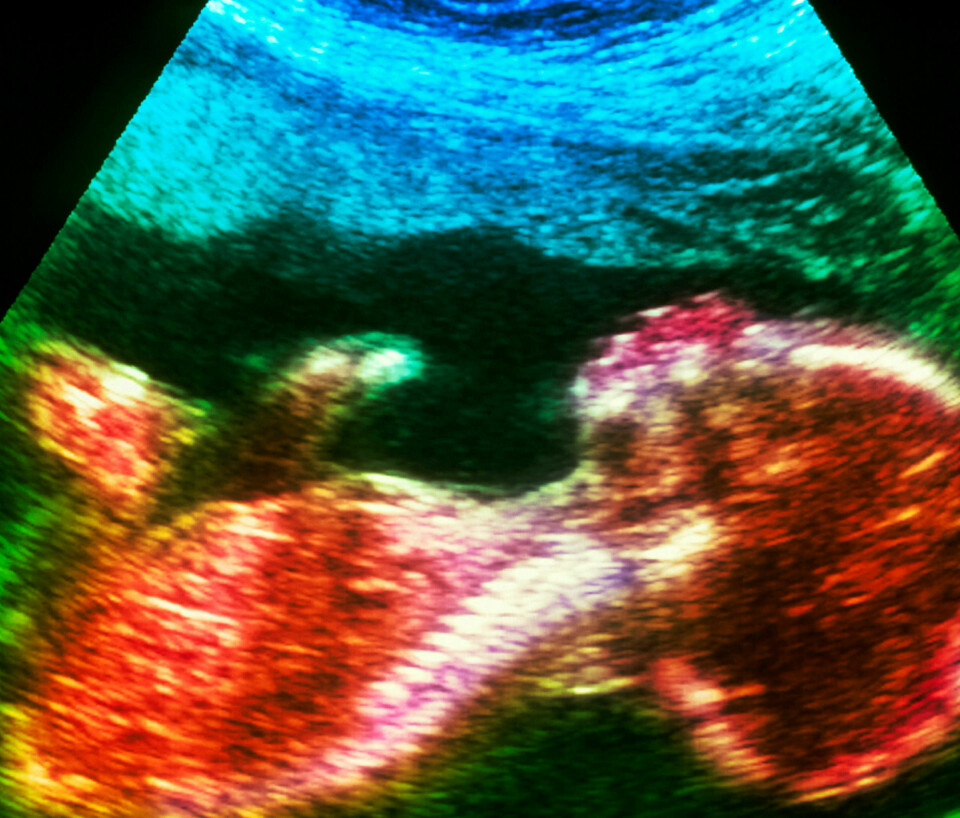

Staten bør legge til rette for at loven er lik for alle mennesker – uavhengig av kromosomer og funksjoner. I dag er det dessverre ikke slik. Oppdager man «noe» ved fosteret man bærer etter grensen for selvbestemt abort, har man adgang til å velge bort opp mot 22. uke. Godt over halvveis i svangerskapet. Menneskeverd ønsker et likestilt lovverk.

Politikken som berører fosterdiagnostikk er i mine øyne på gale veier når man snakker om å utvide regelverket og åpne opp for at alle kvinner kan få tilbud om tidlig ultralyd, når dette for mange handler om å vite om fosteret har en sykdom eller egenskaper man ikke ønsker seg eller makter å ta vare på. Så lenge fosterdiagnostikkens mål i tidlig fase (før uke 12) handler om mulighet til å velge bort på bakgrunn av «funn» på ultralydskjermen og via blodprøver, handler ikke dette om en helsegevinst for barnet. Det blir med andre ord et redskap for å «luke» ut det vi ikke ønsker oss i samfunnet. Det er ikke mangfoldet som lider, men først og fremst enkeltmennesket.